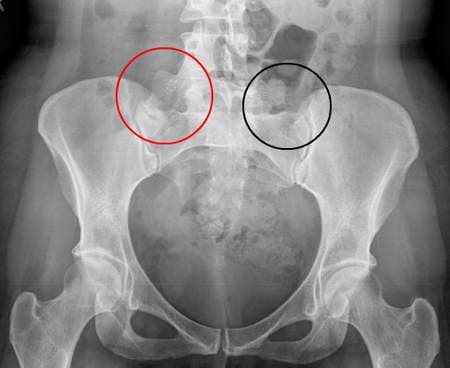

Điều trị viêm khớp cùng chậu như thế nào?

Người bệnh bị viêm khớp cùng chậu thường đau âm ỉ, kéo dài ở vùng cột sống thắt lưng cùng, giữa hai mông và vùng chậu hông khiến khả năng vận động dần bị hạn chế. Điều trị viêm khớp cùng chậu như thế nào, ở đâu tốt, uy tín là mối quan tâm hàng đầu […]

Chữa viêm khớp cùng chậu ở đâu?

Người bệnh bị viêm khớp cùng chậu thường đau âm ỉ, kéo dài ở vùng cột sống thắt lưng cùng, giữa hai mông và vùng chậu hông khiến khả năng vận động dần bị hạn chế. Chữa viêm khớp cùng chậu ở đâu tốt, uy tín là mối quan tâm hàng đầu của những người […]